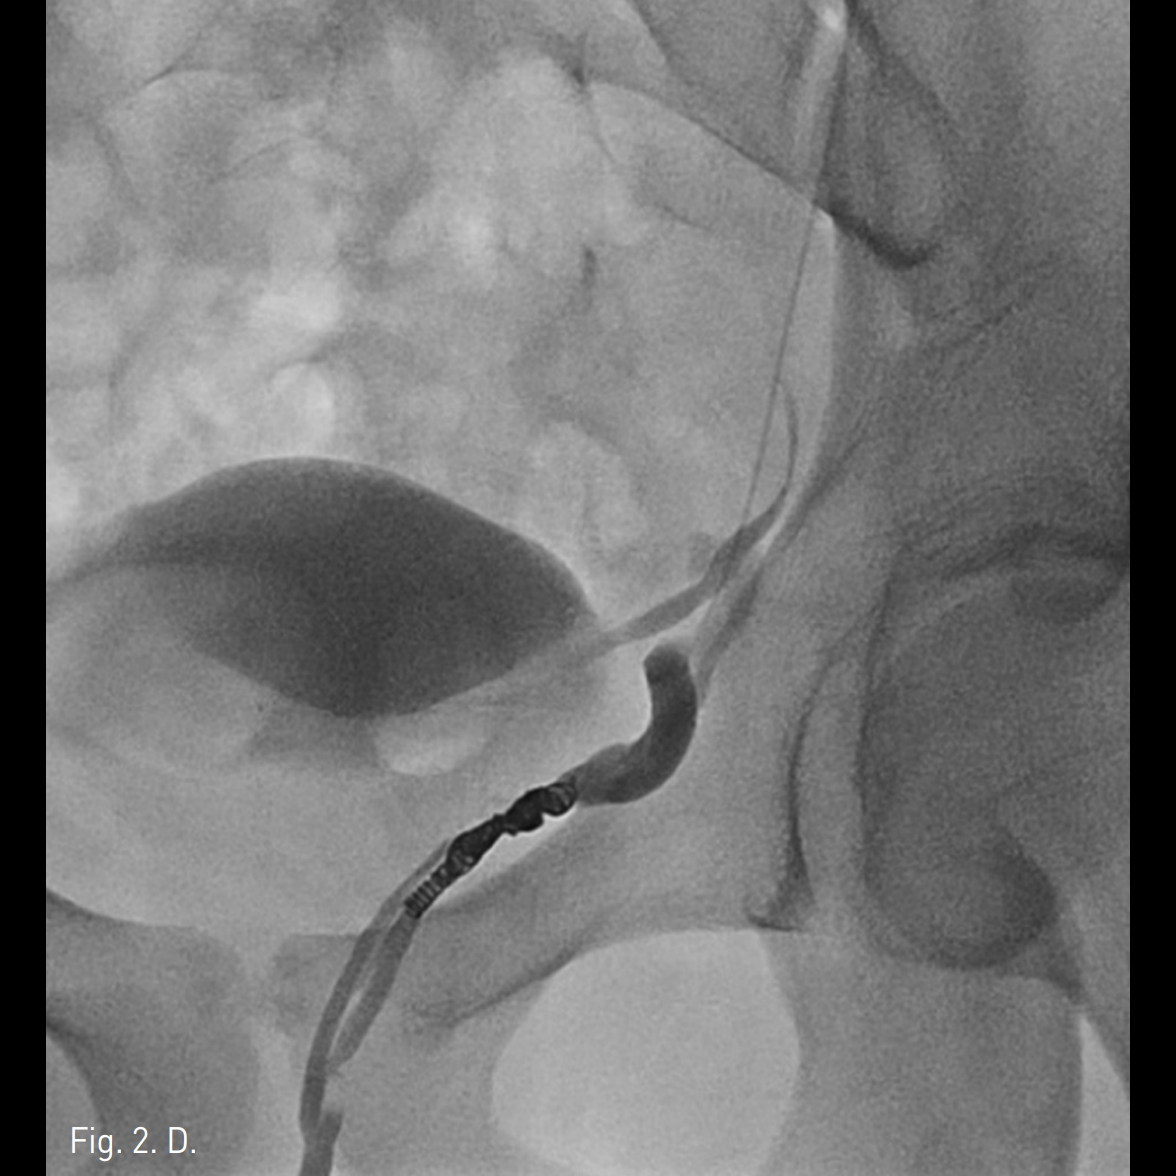

우측 상박을 tourniquet으로 묶은 후 초음파 유도 하에 우측 basilic vein을 minipuncture set을 이용해 천자하여 4Fr Cobra catheter (100cm)를 좌측 신정맥에 위치시킨 후 table tilting을 하여 조영제를 넣었을 때 좌측 spermatic vein.으로의 역류가 관찰되며 L3 level에서 retroperitoneum으로 통하는 venous tributary가 있으며 main tributary는 좌측 pampiniform plexus로 역류되는 소견이 보임(Fig. 2A, 2B). Microcatheter (Renegade, Boston Scientific, Watertown, MA)를 이용하여 보다 자세한 정맥조영을 얻었을 때 inguinal canal level에서 두 개의 정맥이 관찰됨(Fig. 2C). Subinguinal level에서 3개의 microcils (2~3mm ; micronester, Cook, Bloomington, IN)를 이용하여 색전술을 시행하였음 (Fig. 2D). 이어서 환자의 왼쪽 손가락을 이용해 inguinal level을 압박하게 하고 조영제를 주입했을 때 고환으로의 조영제 흐름이 차단된 것을 확인한 후(Fig. 2E), foam sclerotherapy (2mL of 3% STS [sodium tetradecyl sulfate, Thrombojet] + 3mL of air) 5mL를 Cobra catheter를 통해 시행함. 근위부 spermatic vein에 3개의 coils (6mm Nester coils)로 색전술을 시행함. 최종 좌측 신정맥조영술에서 spermatic vein이 조영되지 않음(Fig. 2F).

Fig. 2

C, D. Selective spermatic venograms show two spermatic veins at spermatic cord levd. Three microcoils were deployed in one of the two veins.